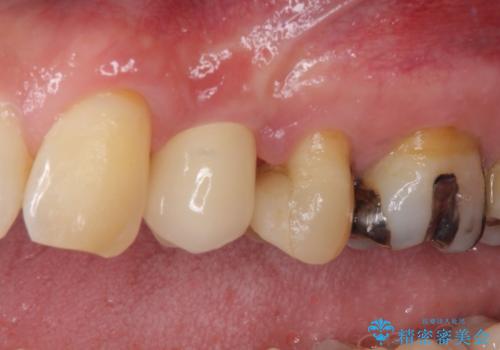

顕微鏡下で診察を行ったところ、歯根が垂直に破折していたため、抜糸してインプラントによる補綴治療を行うこととしました。

ジルコニアカスタムアバットメントは、歯肉ラインに金属が見えにくいというだけでなく、クラウンを装着する土台の形が天然歯と近い形態となるため、清掃性が高く歯肉が腫れにくいというメリットがあります。

インプラントは、人工骨を用いた際の骨誘導能が比較的高いとさせるストローマン社のSLActiveを使用しました。